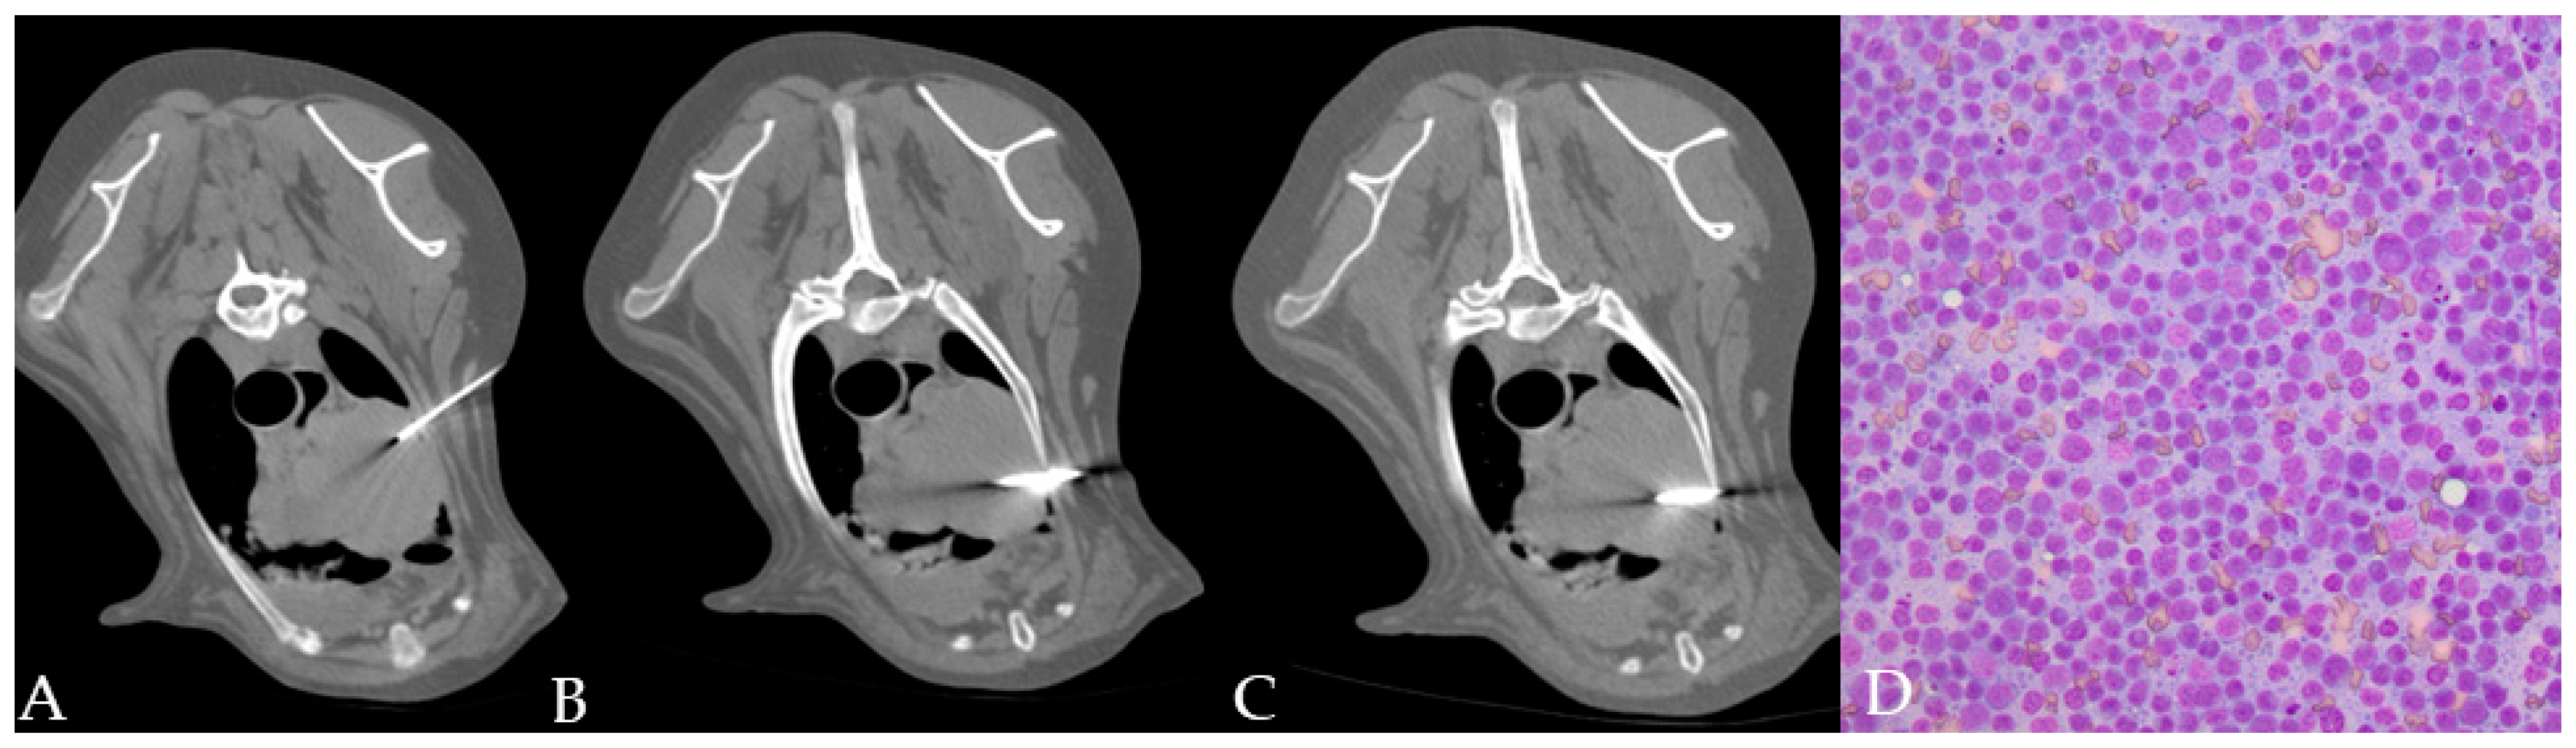

Figure 1.

(A–C) Different phases of the CT–guided biopsy performed in a dog: (A) the dog on the CT table after the surgery was done; (B) the table moved to the selected slice and the laser light guiding the spinal needle insertion; and (C) the semi-automated tru-cut needle inserted into the thoracic wall.